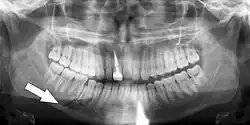

Minimally-displaced fracture in right mandibular. Arrow marks fracture, root canal on central incisor, teeth to the left of fracture do not touch